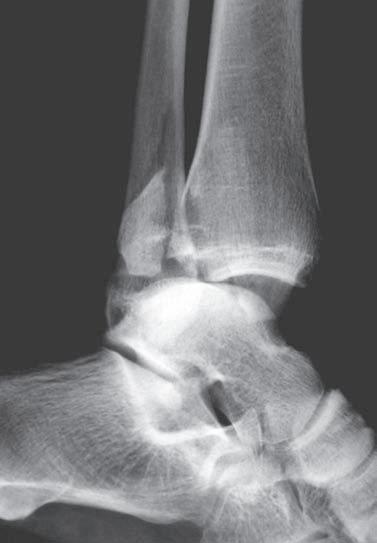

Obr. 2.2 Spirální zlomenina distální části tibie a šikmá zlomenina zevního kotníku. Typ A podle AO klasifikace